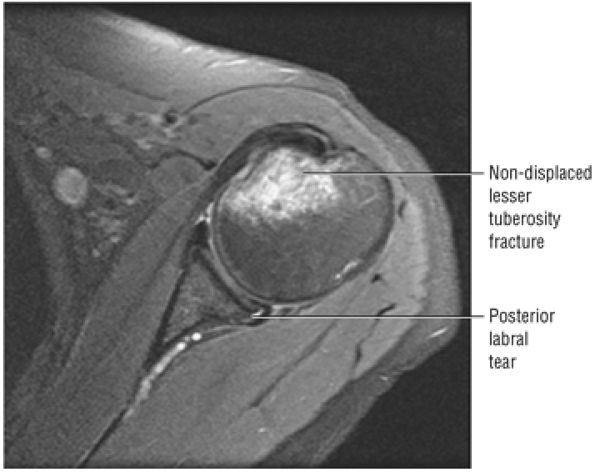

FIGURE 8.102 ● (A) The anterior undersurface of the acromion and the coracoacromial ligament form the coracoacromial arch. The subacromial subdeltoid bursa facilitates the passage of the rotator cuff and proximal humerus under the coracoacromial arch. (B) A superior axial image shows the anterior-to-posterior extent of the coracoacromial (CA) ligament perpendicular to the supraspinatus tendon. The fluid in the subacromial-subdeltoid bursa represents fluid between two serosal surfaces in contact with each other. One serosal surface is contributed by the undersurface of the coracoacromial arch and deltoid, and the other serosal surface is on the bursal side of the cuff.

|

![]() |

FIGURE 8.103 ● Pseudospur. The normal broad attachment of the coracoacromial ligament to the inferior surface of the acromion is shown on (A) T1-weighted coronal oblique and (B) sagittal oblique images. The low-signal-intensity acromial cortex (black arrows) and adjacent coracoacromial ligament and lateral slip of the deltoid attachment (white arrows) give the false impression of a small subacromial spur in the coronal plane. This pseudospur should not be misinterpreted as impingement; otherwise, unnecessary acromioplasties may be performed on patients with a normal coracoacromial ligament attachment and no associated acromial spurs.